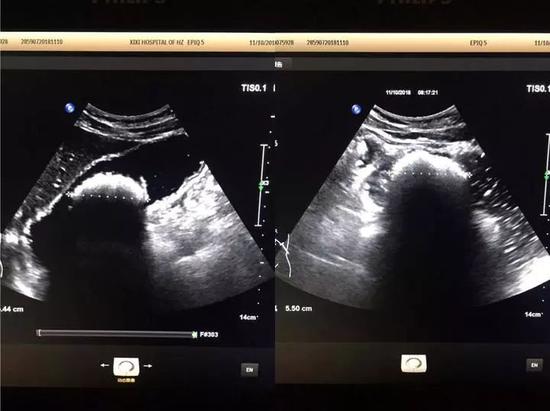

第三天,腹痛越加明顯,小張如約趕到市西溪醫院超聲科,潘林醫生給他仔細做了檢查,肝臟、膽囊等臟器一個個查過來都沒什么問題,一直查到腹部時,發現了一個“大家伙”,再放大鏡頭看,竟是胃里有個直徑5.5cm的結石。

亮亮的一團就是胃結石根據經驗,潘醫生建議小張去做胃鏡,鏡下把大結石切碎,然后可以直接取出,也可以待其由消化道排出。小張一聽,頓時慌了:“醫生,做胃鏡太難受了,還有別的辦法嗎?”看著小張一臉的抗拒,潘醫生就跟他提了“可樂療法”。

在消化科醫生的指導下,小張很快開始“可樂療法”。吃完早飯后先吃一顆保護胃粘膜的藥,休息個半小時后,喝一瓶500毫升的可樂,接著中午正常飲食,到下午茶時間再喝一瓶500毫升的可樂,晚上依然是正常吃飯。就這樣,什么罪都沒遭,什么事也沒耽誤,每天只是比平時多喝了兩瓶可樂,申請的變化正在小張肚子里慢慢發生。三天后,他的腹痛癥狀緩解了;六天后,再復查B超,胃里的“大家伙”竟已不見蹤影。